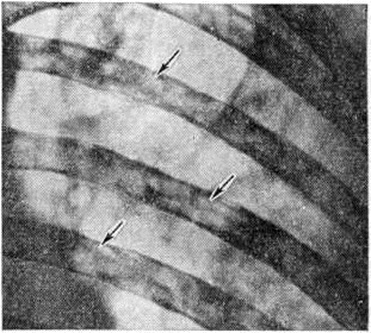

Рис. 9.

Рентгенограмма (фрагмент) грудной клетки при миеломной болезни (прямая проекция): видны множественные нечётко очерченные деструктивные очаги в рёбрах (указаны стрелками).